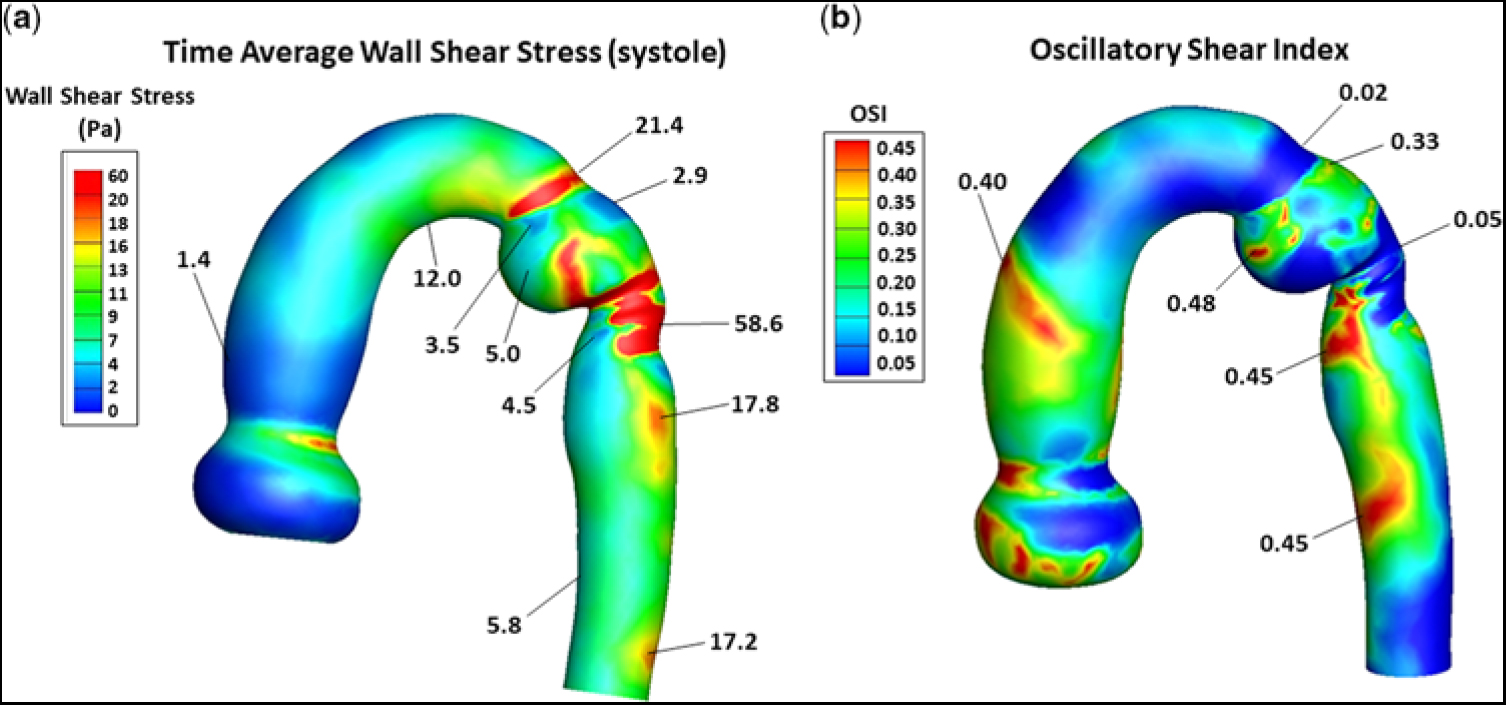

Figure 5a provides a contour plot of the TAWSS, in Pascals, for the entire computational domain, prior to stent implantation. In the ascending aorta, just above the sino-tubular junction (dark blue region), TAWSS was low (∼1.4 Pa), typical for an unobstructed ascending aorta. As flow advanced along the curved under surface of the transverse aortic arch (green region), TAWSS increased (∼12 Pa). When flow turned and entered the isthmus (red-ringed region), TAWSS increased further (∼21.4 Pa). However, on the adjacent lateral (outer) wall, just beyond the entrance to the isthmus (small dark blue region), TAWSS decreased nearly 10-fold (∼2.9 Pa). This area represents the proximal portion of the subclavian flap aortoplasty. The TAWSS was also relatively low (∼3.5 Pa) on the juxtaposed medial wall of the ampulla (small blue/green region). This is the location where flow detached from the aortic wall as it entered the enlarged ampulla/isthmus. TAWSS then dramatically increased (∼58.6 Pa) just beyond the junction of the isthmus and the thoracic descending aorta (prominent red region). This is the site where the emerging high-velocity (∼2.8 m/second) jet impinged on the lateral wall of the aorta – recall Figure 3a. As flow progressed along the descending aorta, two areas of elevated TAWSS (∼17.8 and ∼ 17.2 Pa) emerged on the lateral wall (orange regions), downstream from the re-coarctation. Moreover, the high-velocity central stream in the descending aorta also gave rise to low-velocity re-circulating (retrograde) flow that induced relatively low TAWSS (∼4.5 Pa) near the medial wall (blue region). Such a heterogeneous distribution of wall shear stress in the thoracic descending aorta can weaken the structure of the aortic wall by disrupting its extracellular matrix.

Figure 5. (a) Contour plot of TAWSS, in Pa, and (b) the distribution of OSI, for the entire computational domain, and prior to stent implantation. In (a), representative values of TAWSS are shown without the units. The units are (Pa). In (b), OSI has no units. The triads of low flow velocity, low TAWSS, and high OSI and high flow-velocity, high TAWSS, and low OSI have important pathological implications, as described in the Discussion. OSI = oscillatory shear index; TAWSS = time average of wall shear stress.

Figure 5b shows the distribution of oscillatory shear index, for the entire computational domain, and prior to stent implantation. It ranged between 0 and 0.45, where 0 denotes a unidirectional and 0.45 a multidirectional wall shear stress vector. A value of ∼0.3 or greater implies a wall shear stress vector undergoing substantial change in direction over the cardiac cycle. In the ascending aorta above the sino-tubular junction, a narrow band (orange region) of high oscillatory shear index (∼0.4) was present, reflecting flow’s encounter with the curved portion of the ascending aorta. As flow advanced along the under surface of the transverse aortic arch and at the entrance to the isthmus (dark-blue regions), oscillatory shear index remained very low (∼0.02), consistent with the instantaneous wall shear stress vector being oriented in the time-averaged direction over the cardiac cycle. However, on the adjacent lateral wall of the isthmus (small green region), oscillatory shear index increased considerably (∼0.33). This area of higher oscillatory shear index coincided with the area of low TAWSS (∼2.9 Pa) shown in Figure 5a. Then, at the site where the high-velocity jet emerged from the isthmus to strike the lateral wall of the aorta (dark blue region), oscillatory shear index decreased dramatically (∼0.05). This area of low oscillatory shear index coincided with the area of markedly elevated TAWSS (∼58.6 Pa) shown in Figure 5a. As flow progressed further along the descending aorta, two areas on the medial wall (red regions) had high oscillatory shear index (i.e., ∼0.45). These areas of high oscillatory shear index coincided with the areas of relatively low TAWSSs (∼4.5 and ∼5.8 Pa) shown in Figure 5a. Thus, sites of low oscillatory shear index tended to be associated with high TAWSS, and conversely high oscillatory shear index was coupled with low TAWSS. The inverse relationships between these shear stress metrics have important clinical implications.